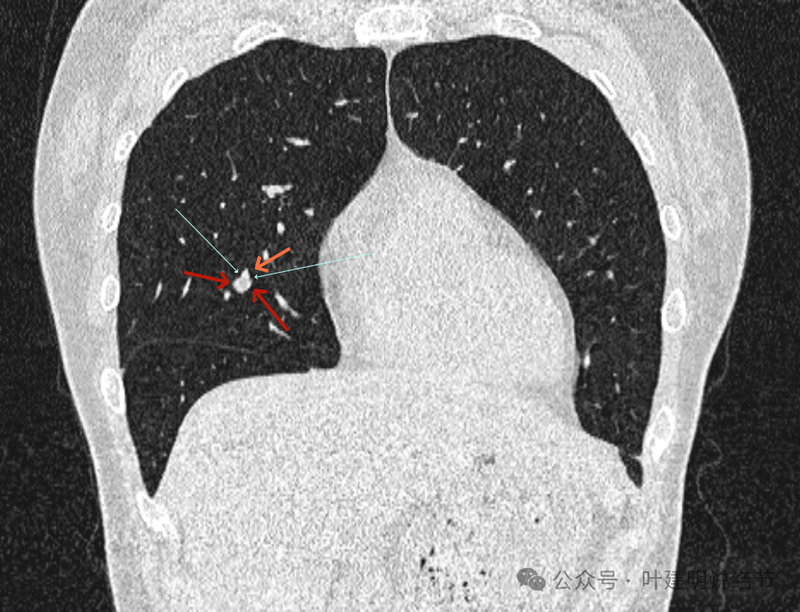

再看冠状位影像:

血管与病灶的关系,两者密度稍不同,天蓝色细箭头所指是分界线。

血管征明显。

血管围着病灶,病灶有膨胀性,表面欠平滑。

不而有膨胀性,血管贴着并被压迫。

边缘欠平滑,邻近血管间隙欠清晰。

血管贴着,结节膨胀。

也示血管与病灶的关系。

结节实性。

纵隔窗这个角度明显见到蓝色箭头所指的血管被病灶侵蚀,而且血管与病灶密度的不同。